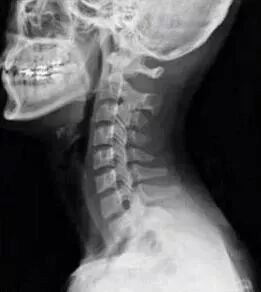

大家都知道,颈椎的正常生理曲度是前凸的,而胸椎是后凸的。在颈胸交界刚好是前凸后凸的交界,当颈椎下段过度前凸而胸椎上段过度后凸时就形成了骨性的颈胸交界骨性突起。

(正常的颈椎图)

这样的骨形突起直接影响到附着的肌肉,相关的肌肉群也会因此紧张痉挛而肿胀,两边的第一第二肋骨也因此而翻转,椎肋间的肌肉群肿胀痉挛,甚至翻转的肋骨还波及斜角肌以至于斜角肌间隙变得狭窄。这样肌肉的肿胀使得这个骨性的突起变大并且更加突出,“富贵包”就此成型。